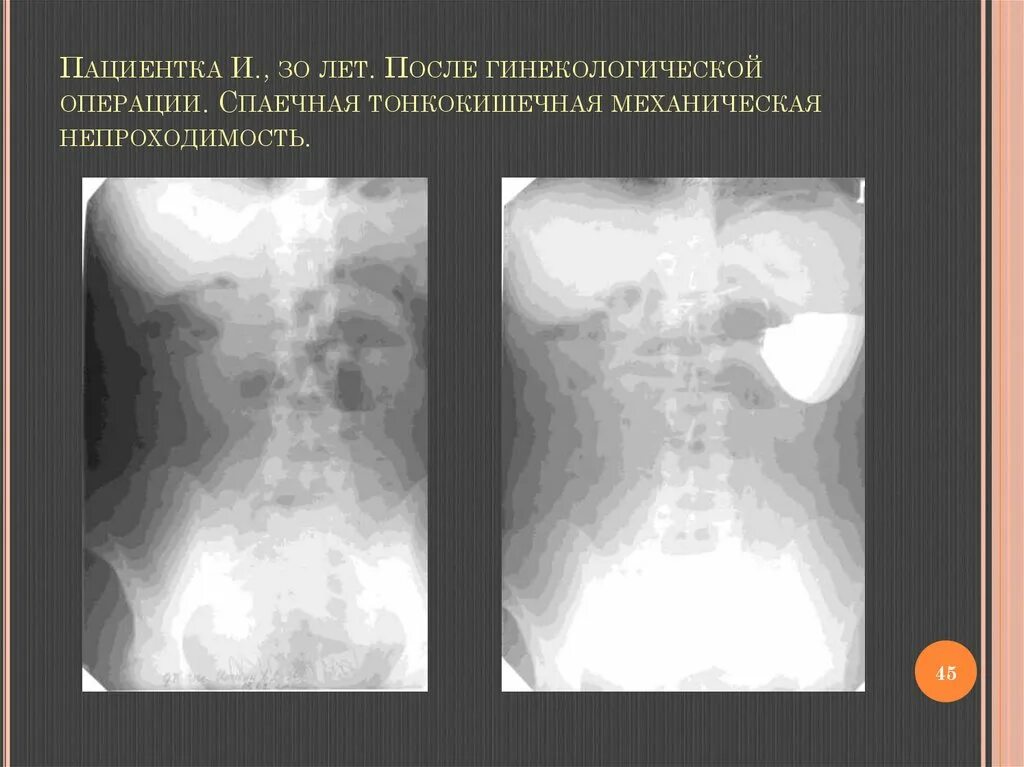

Спаечная кишечная непроходимость мкб